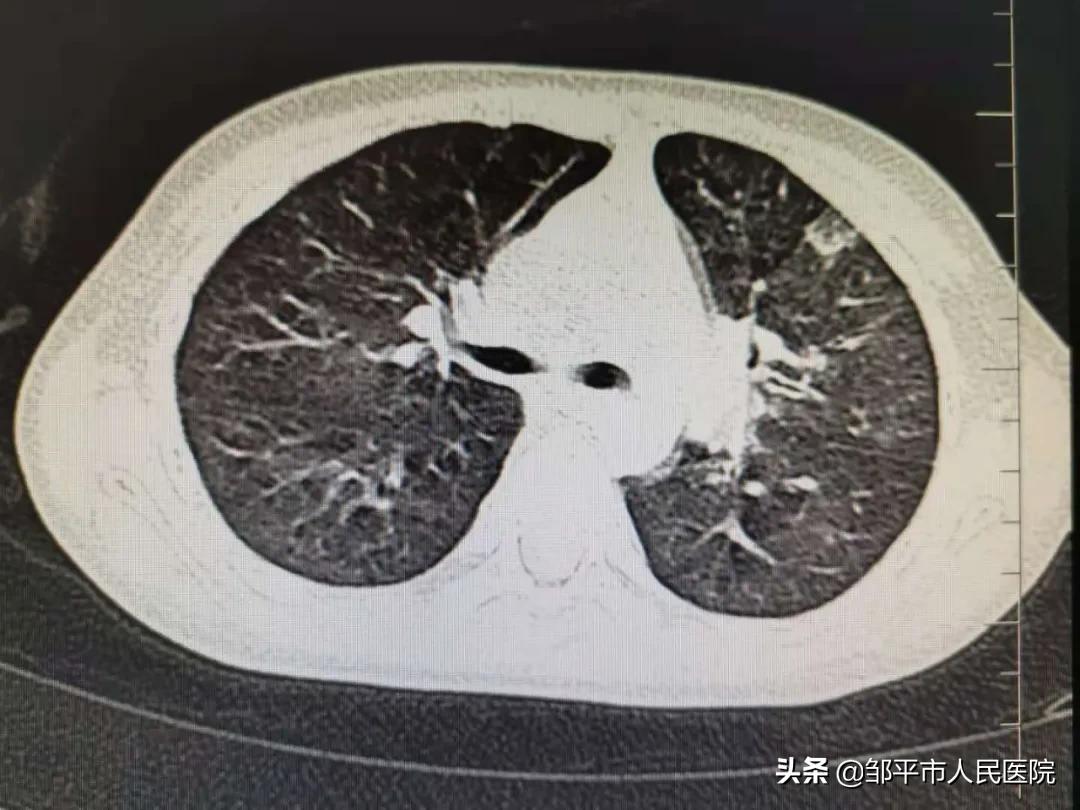

清洗后

两名患儿的体温很快降至正常,咳嗽咳痰消失,复查胸部CT肺脏完美复张,孩子们均康复出院。